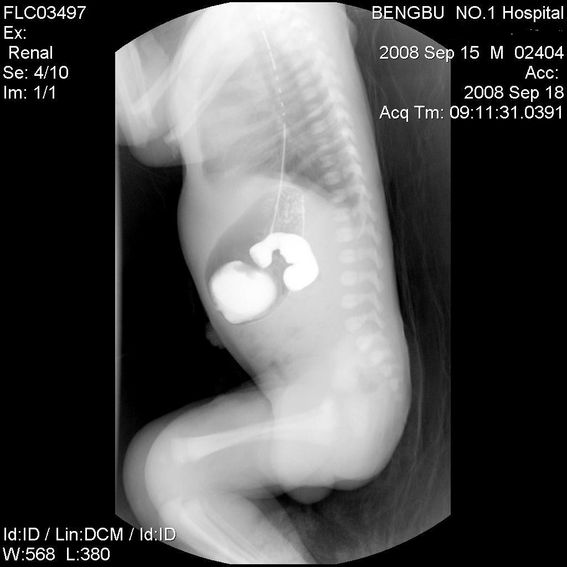

十二指肠降部钡流不能顺利通过,胃及十二指肠球扩张。

考虑----十二指肠降部狭窄-----〔但这几个片子狭窄未能清楚显示,无法判断分型-----膜性或管状〕

考虑----十二指肠降部狭窄

十二指肠降部狭窄(可能为环状胰腺)。

十二指肠降部钡流不能顺利通过,胃及十二指肠球扩张,符合十二指肠降部狭窄